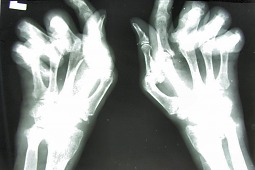

Chodzi o programy lekowe. Konkretnie o program dotyczący RZS. Ministerswo Zdrowia chce zaostrzyć kryteria dostępu do programów. Protestuje przeciw temu PolskieTowarzystwo Reumetologiczne.